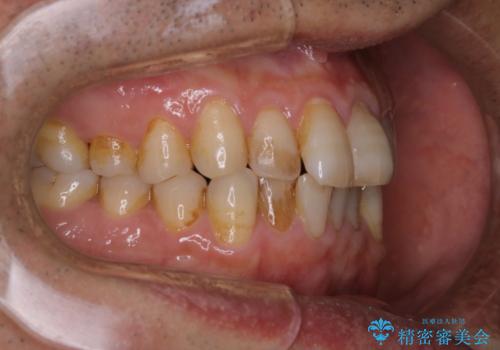

全体的にプラークや歯石が付着していて、歯肉炎が見られました。

状態に合った専門的な器具を使用して、歯質や歯肉へのダメージを抑えながらPMTC(自費クリーニング)60分コースを行いました。矯正治療後の保定装置がワイヤーの場合、フロス・糸ようじが通せないこと、歯ブラシがしずらいことなどにより、歯石プラークなどが付着しやすくなります。そのため専門的な器具による細かいケアを行うことがとても大切です。